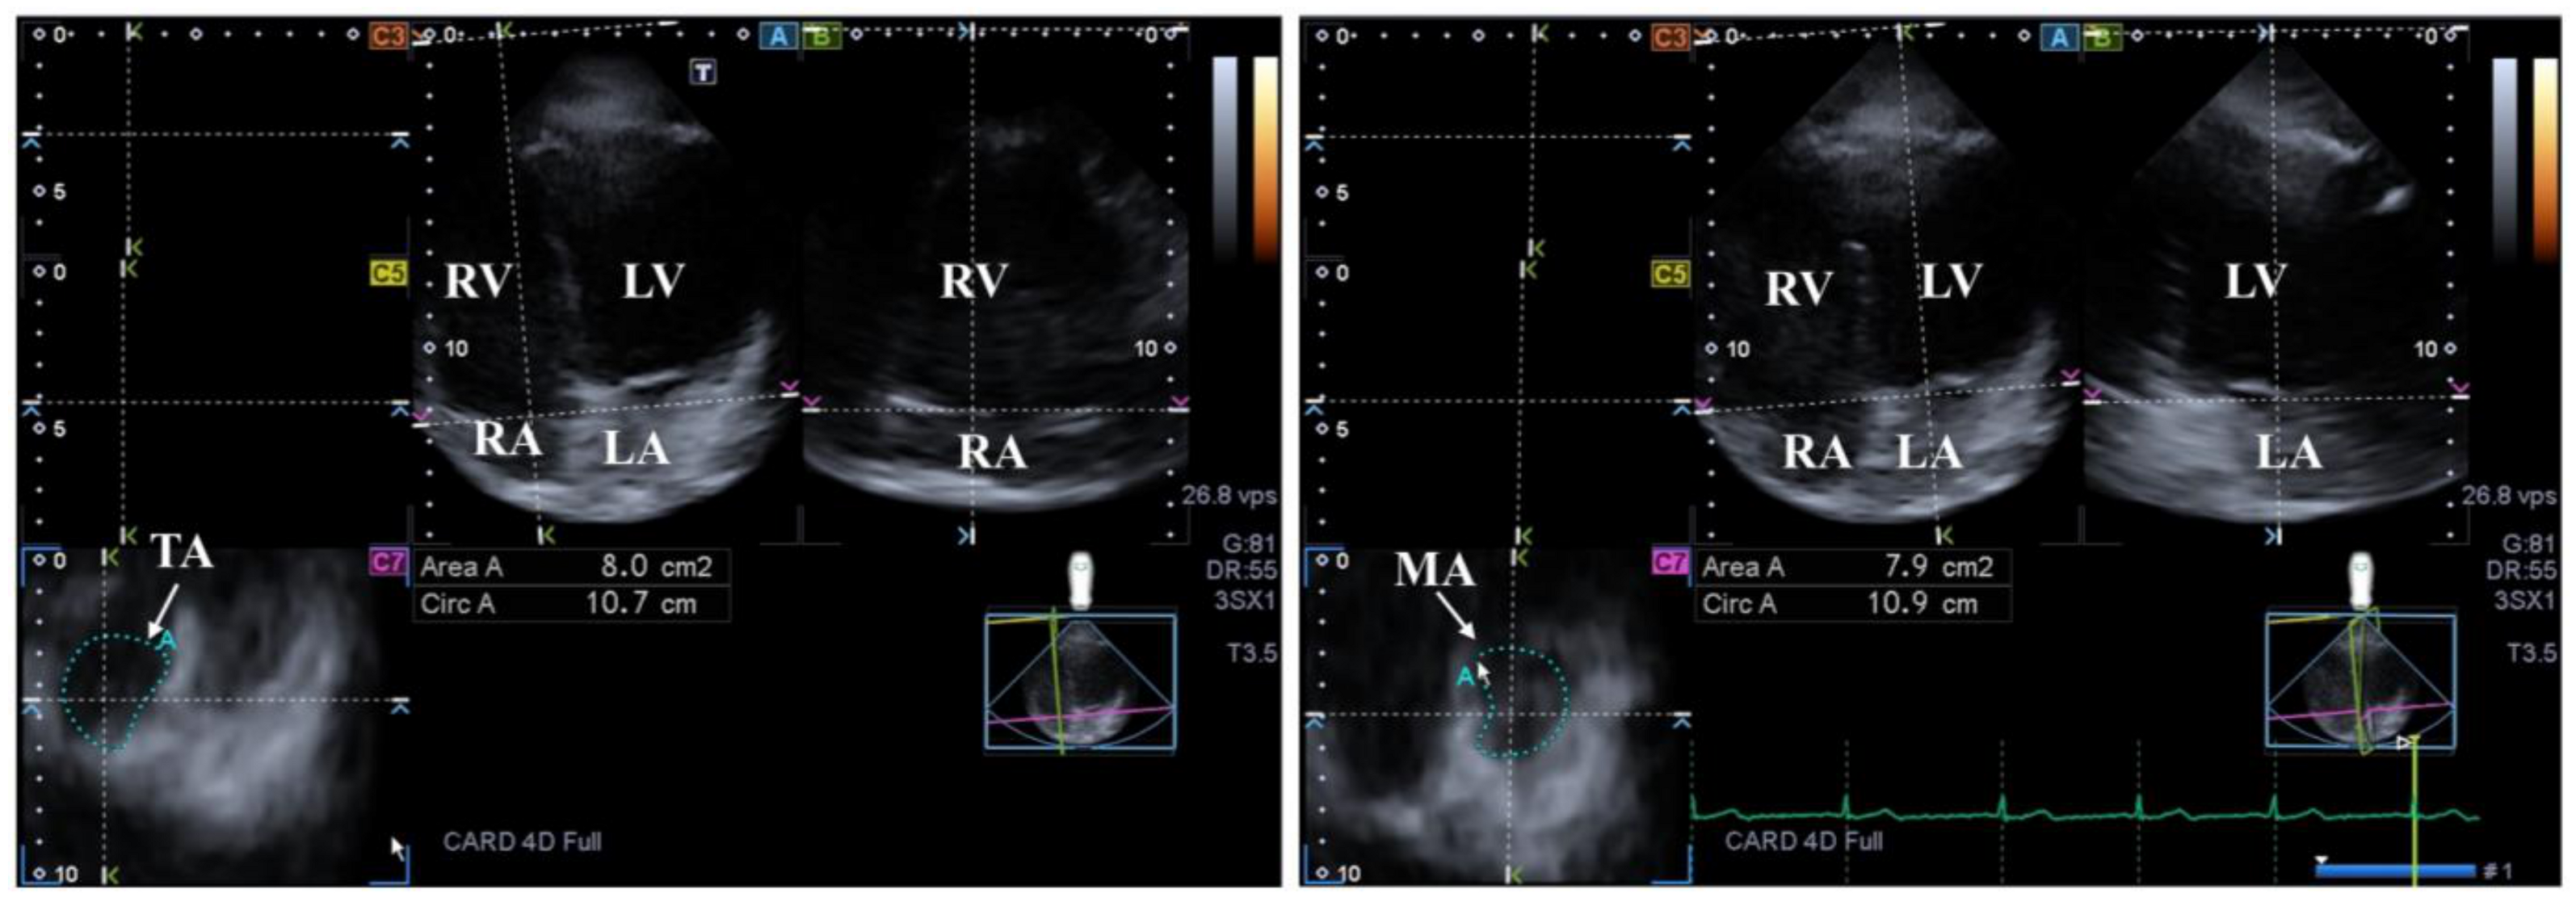

The MV has several components: two leaflets, a subvalvular apparatus consisting of chordae tendinae and papillary muscles and a saddle-shaped annulus (MA) that has a dynamic motion respecting the heart cycle. The MV opens/closes during diastole/systole with one-way flow of blood from the LA into the LV in normal healthy circumstances. Adjacent regions of these heart chambers have a significant role in the contraction of MV [16,59,60] (Figure 3).

Figure 3.

Examination of the tricuspid (TA) and mitral (MA) annuli by three-dimensional (3D) echocardiography (left panel and right panel, respectively). (A) Apical 4-chamber and (B) two-chamber longitudinal views help visualization of valvular annuli on (C7) cross-sectional view. TA and MA planes are marked by a white arrow. TA and MA can be easily detected alongside the heart chambers including the left ventricle (LV) and atrium (LA) and the right ventricle (RV) and atrium (RA).